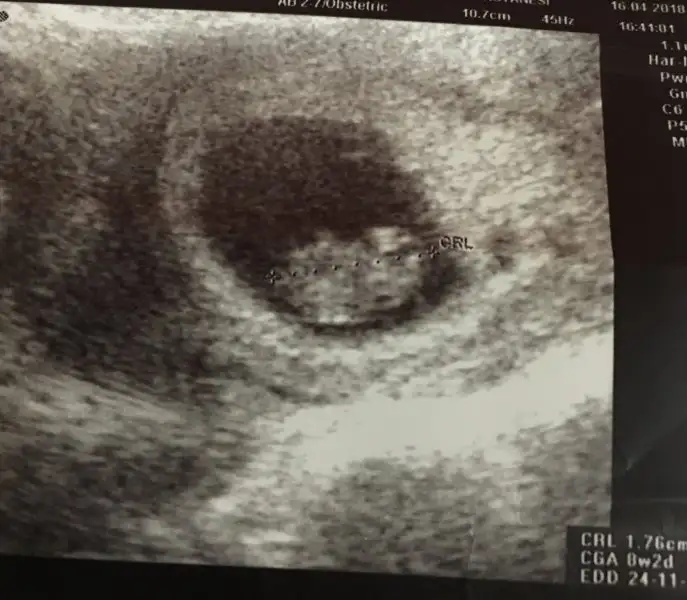

7.hafta usg bakabilirmisiniz?

kizlar lutfen bnm bebisin cinsiyeti hakkinda da tahmin ve yorum yapin.

gün gecmiyor sabirsizliktan gebercem. 8 haftalik usg yukledim.

Kızlar banada yorum yapın 8 haftalık ramzi teorisine göre yorumlanınca ne oluyor cinsiyet karından bakıldı